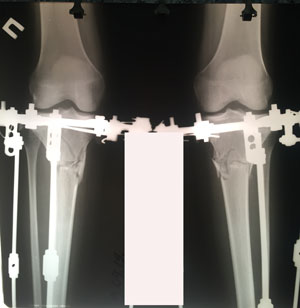

Исходник - 29 лет.

Дата операции - 12.08.2019.

Ротация с обеих сторон.

Рентген пере снятием аппаратов!

Дата снятия аппаратов 05.2.2019.